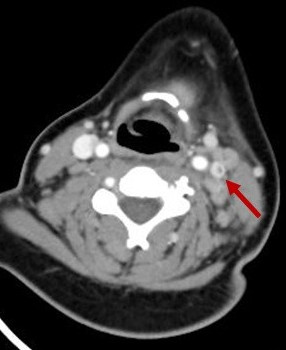

En la exploración física presenta edema retroauricular izquierdo, sin despegamiento del pabellón auricular, adenopatía submandibular izquierda dolorosa y en la otoscopia izquierda se visualiza el tímpano abombado y deslustrado. Se realiza analítica sanguínea en la que destaca: proteína C reactiva 16,78 mg/dl, procalcitonina 0,17 ng/ml, leucocitos 19 800/mm3 (neutrófilos 77,4%). Se decide ingresar a la paciente en planta de hospitalización e iniciar tratamiento con amoxicilina-clavulánico intravenoso. A las 24 horas del ingreso presenta empeoramiento clínico con aparición de tumefacción laterocervical izquierda de unos 2-3 cm de diámetro, caliente y dolorosa, junto con limitación a la movilización cervical. Es valorada por el servicio de otorrinolaringología y se indica realización de tomografía computarizada (TC) cervical urgente, que muestra una otomastoiditis izquierda, trombosis yugular interna izquierda (Figs. 1 y 2) y adenoflemón izquierdo.

Figura 2. Imagen de TC (corte sagital) en la que se visualiza trombosis yugular interna izquierda (flecha)